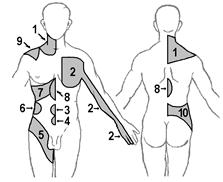

Ноцицептивная стимуляция внутреннего органа часто вызывает ощущение боли не в нем самом, а в отдаленных, поверхностных частях тела, или не только в нем самом, а также в отдаленных частях тела. Такая боль называется отраженной. Как правило, она охватывает участки периферии, иннервируемые тем же сегментом спинного мозга, что и затронутый внутренний орган. Иными словами, на поверхности кожи боль проявляется в соответствующем дерматоме (рис.).

Рис.. Дерматомы. Вид спереди.

Рис.. Дерматомы. Вид сзади.

Поскольку связь между дерматомами и внутренними органами известна, отраженная боль часто очень помогает при диагностике заболеваний внутренних органов. В 1889 г. знаменитый русский клиницист Г.А.Захарьин впервые обратил внимание на то, что на поверхности тела существуют участки, на которые проецируются болевые ощущения при патологии определенных внутренних органов (рис.). Подробное описание этих зон было сделано в 1893 —1896 гг. Г.Гедом и в настоящее время они получили название зон Захарьина — Геда [Б20].

Рис.. Схема расположения на туловище и конечностях некоторых зон Захарьина-Геда, в которых может появляться отраженная боль при ряде заболеваний внутренних органов[Б21]: 1 — легкие и бронхи, 2 — сердце, 3 — кишечника, 4 — мочевого пузыря, 5 — мочеточника, 6 — почек, 7 и 9 — печени, 8 — желудка, поджелудочной железы, 10 — мочеполовой системы[Б22].

Установлены следующие соотношения между внутренними органами и сегментами кожной иннервации (напр., легкое — III — IV шейные и II — V грудные, сердце — III —V шейные и I — VIII грудные, тело матки — Х грудной и I поясничный).